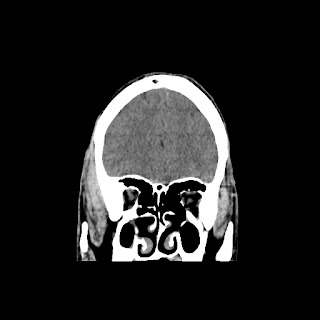

CT scan of brain images:

Repeat radiological images: